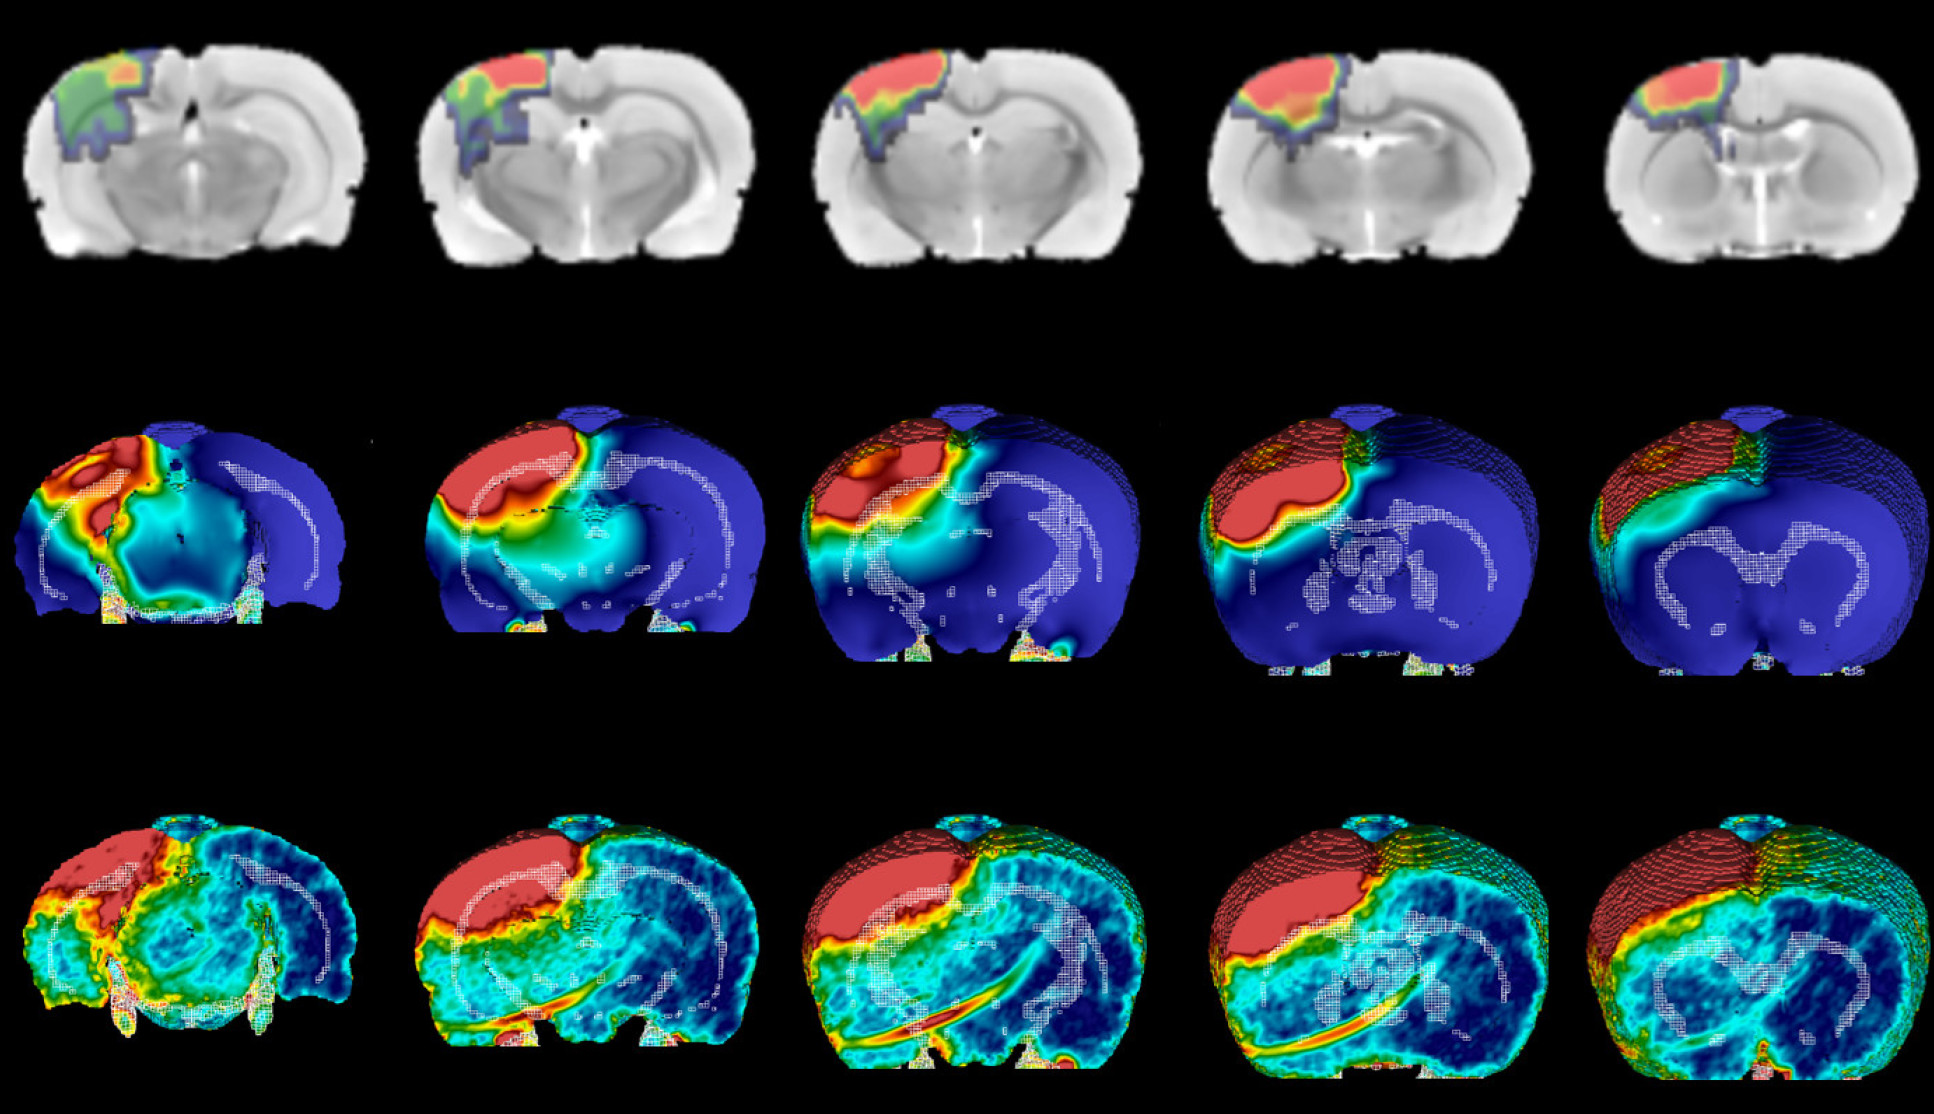

Imaging and computational models depicting the development of brain injury after a moderate impact on rat brains.

Development of injury after moderate impact

Now, they have tested this modelling approach to see if it can accurately predict the pattern of white matter damage in rats given mild or moderate TBI. They simulated the rats’ brains during injury, revealing the location and duration of mechanical forces linked to damage. Using a precise experimental model, this damage was induced in the rat brain and followed up after several weeks, which correlates to years of changes in a human brain.

They found that the effect of shear stresses on the white matter helped to predict the location of long-term damage. Shear stresses push two parts of the same object, in this case the brain, in different directions.

Dr Magdalena Sastre, from the Department of Brain Sciences at Imperial, said: “The shear stresses on the brain correlated with markers of brain inflammation, which is associated with memory loss and other future functional cognitive alterations.”